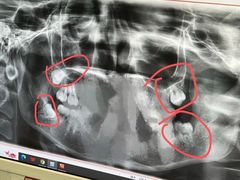

• 维乐口腔(格林门诊长宁店)

• -维乐口腔(格林门诊长宁店)